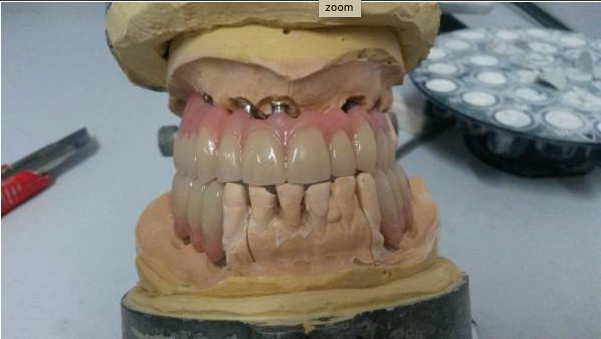

III fase, posizionamento della protesi sugli impianti: fase chirurgica: con il supporto del Laboratorio Odontotecnico Design Dentale (www.designdentale.it) e della Dottoressa Daniela Gasparini, entro poche ore saremo in grado di fissare gli elementi dentali direttamente sugli impianti inseriti durante la prima fase chirurgica. Ogni protesi è personalizzata e il risultato estetico sarà assolutamente naturale: questo è possibile anche grazie allo studio del caso preliminare effettuato pre-intervento con l’ausilio di foto ed impronte di ogni singolo paziente e tecnologia digitale CADCAM.

Ci preoccupiamo di rendere ogni lavoro unico, diverso e personalizzato. Perchè ogni sorriso e ogni bocca è differente. Ti verranno prese delle impronte preliminari che verranno inviate al laboratorio; Verranno scattate delle foto per analizzare al meglio la fisionomia del viso; Ti verrà fatto scegliere il colore dei nuovi denti che preferisci e che meglio si sposa con le caratteristiche estetiche della persona.

La protesi che ti verrà consegnata il giorno dell’intervento, anche se provvisoria, dovrà essere quanto più possibile perfetta e rispecchiare in pieno i desiderei e le aspettative del paziente

Il Chirurgo sarà sempre affiancato da un protesista esperto in protesi da carico immediato e dai tecnici del laboratorio che realizzano manufatti da carico immediato da tantissimi anni e con la massima qualità. Per fare in modo che vada tutto alla perfezione, non sono importanti solo gli impianti ma anche le protesi fisse che vengono avvitate sugli stessi.

Spesso non viene indicato che, nel carico immediato, c’è bisogno di una doppia protesi: una provvisoria fissa in resina che viene applicata il giorno dell’intervento e una definitiva con barra in titanio o cr-co che viene applicata dopo sei mesi. Quest’ultima sarà molto più resistente e molto più duratura e andrà a rimpiazzare la protesi fissa provvisoria iniziale.